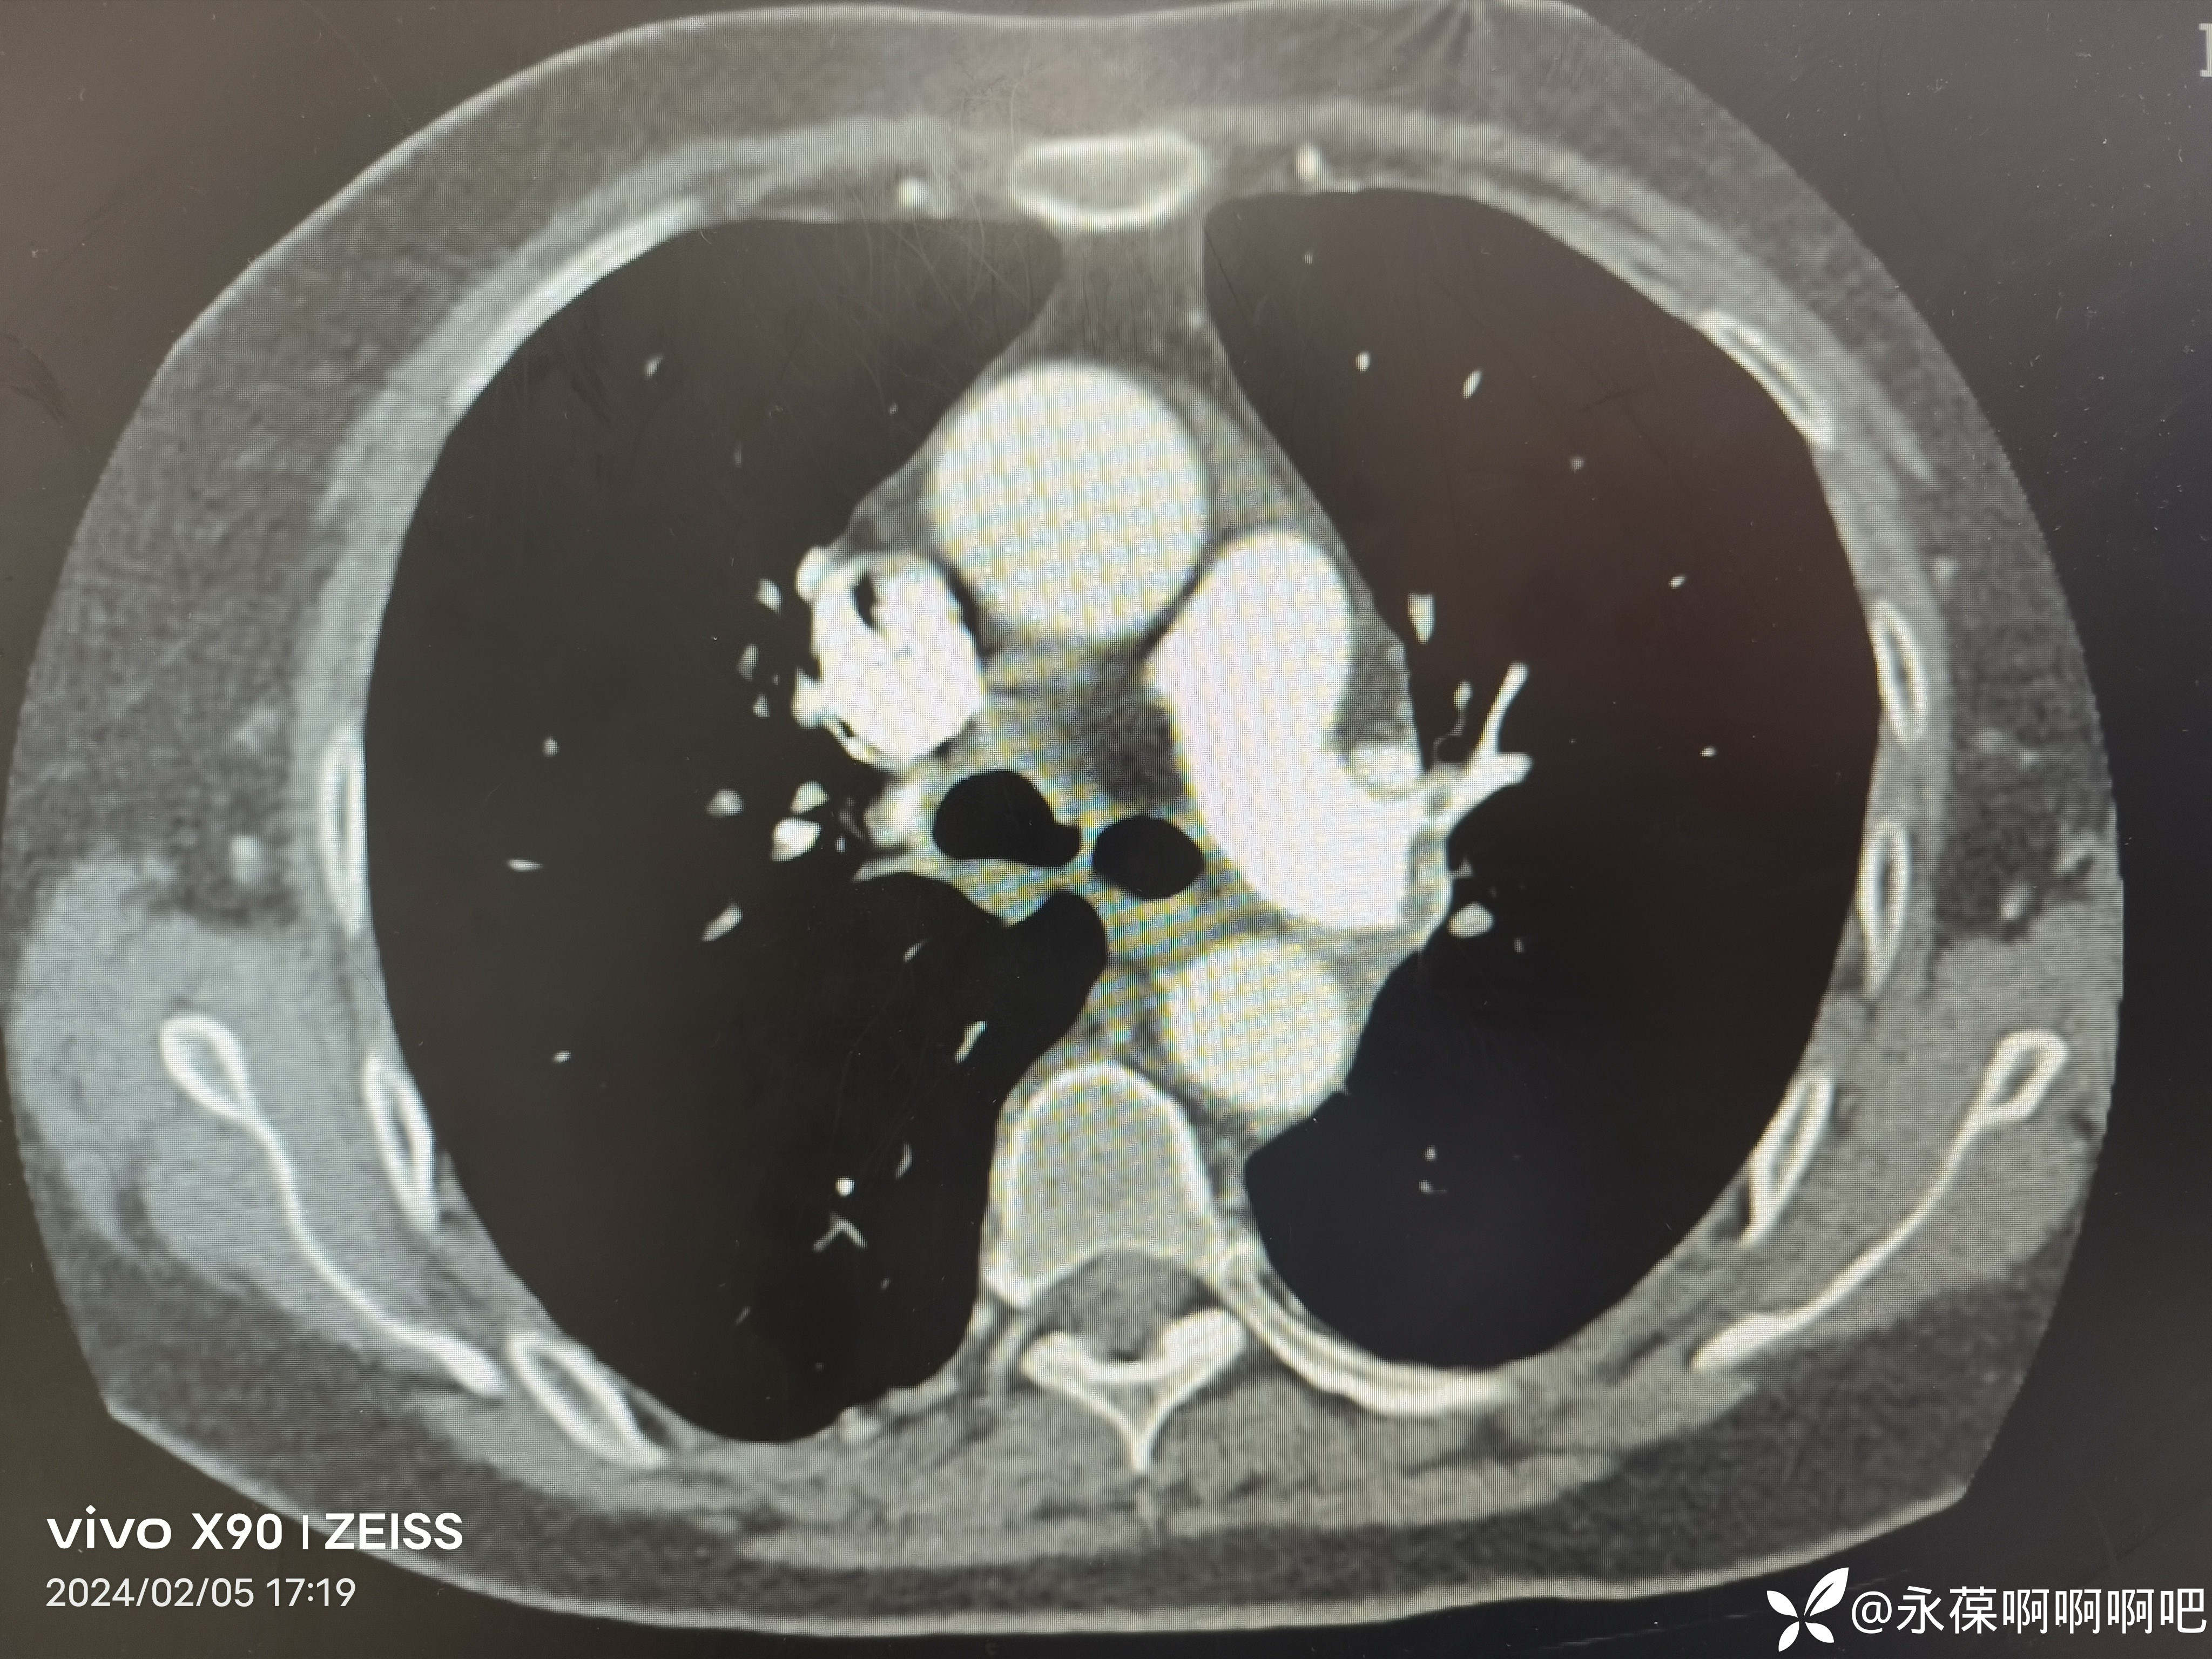

肺动脉CTA:左右肺动脉干及其分支多发栓塞。